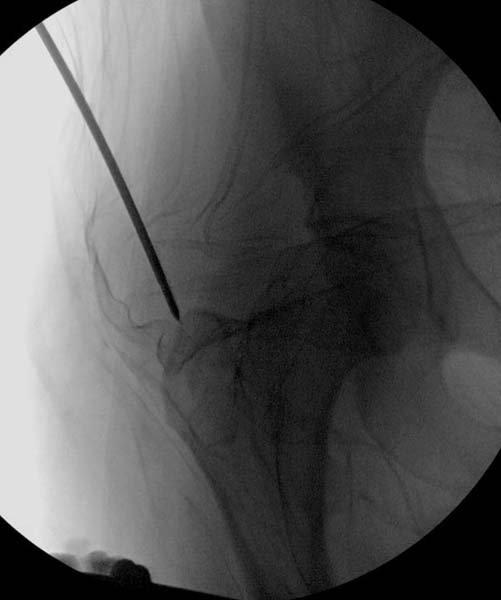

> Больная стабильная после хирургических мероприятии и получив добро,

> приступили к закрытому вправлению таранной кости с укладкой наружного

> фиксатора. Затем укладка больную на бок и открытый остеосинтез